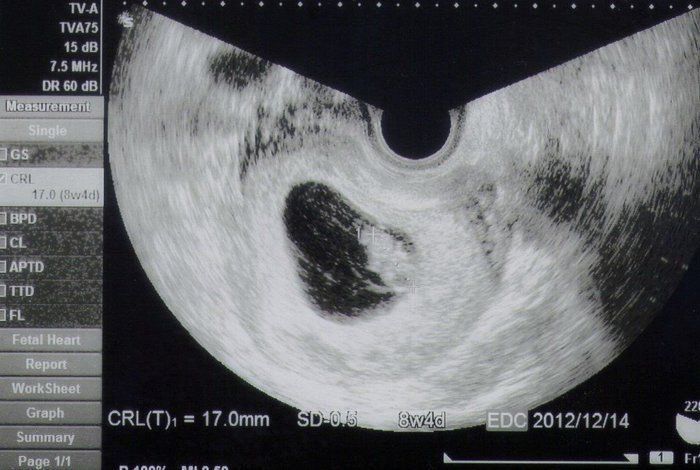

8週4日目 エコー

8週4日目 エコー- 今日は妊婦検診でした。今日で8週と4日目です。 ところが前回まではっきりと確認できていた心拍が今回は確認できず。 胎児はしっかりと週数通りに大きくなっているのですが・・・。 自分でもエコーを見た瞬間に分かりました。排卵後 16日目 妊娠4週2日 超音波検査で胎胞(GS)が見えてきます(15mm) 排卵後 17日目 妊娠4週3日 以後妊娠5週0日まではGSは毎日1mmずつ大きくなります 妊娠5週目以降は、GSの成長が人によって異なります 排卵後 23日目

38 週 4 日 エコー 妊娠8週4日(8w4d)の超音波(エコー)写 妊娠8週4日(8w4d)の超音波(エコー)写真 妊娠8w4d 名前Monri 年齢38 妊娠週8w4d 初期で何かと心配な時期ということで前回から1週間後に再診。順調に177cmへ成長していました!心拍も問題なし。 9週4日(9w4d・男の子)|もぞ1224 さん(29歳) エコー写真撮影時のエピソード: はじめに受審したときのエコー写真は、小さな豆粒のようなものがうつっていた。それからそんなに時がたたないうちに、人の形になって小さな生命を実感した。ママにエールさんの妊娠7週目のエコー写真 2度"逆子"になった胎児はもう小学生! 子どもと共に読み返した当時の日記&エコー画像 画像中央のとの間が赤ちゃんで、上の丸い頭のようなものが赤ちゃんに栄養を送る袋(卵黄嚢)だと教えてもらいまし

妊娠8週4日 8w4d の超音波 エコー 写真

8週4日 9週のエコー写真 食べブログ